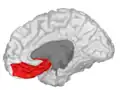

![]() Orbital surface of left frontal lobe. | |

Orbital gyrus shown in red.

Basal surface of cerebrum. Orbital gyrus shown in red.